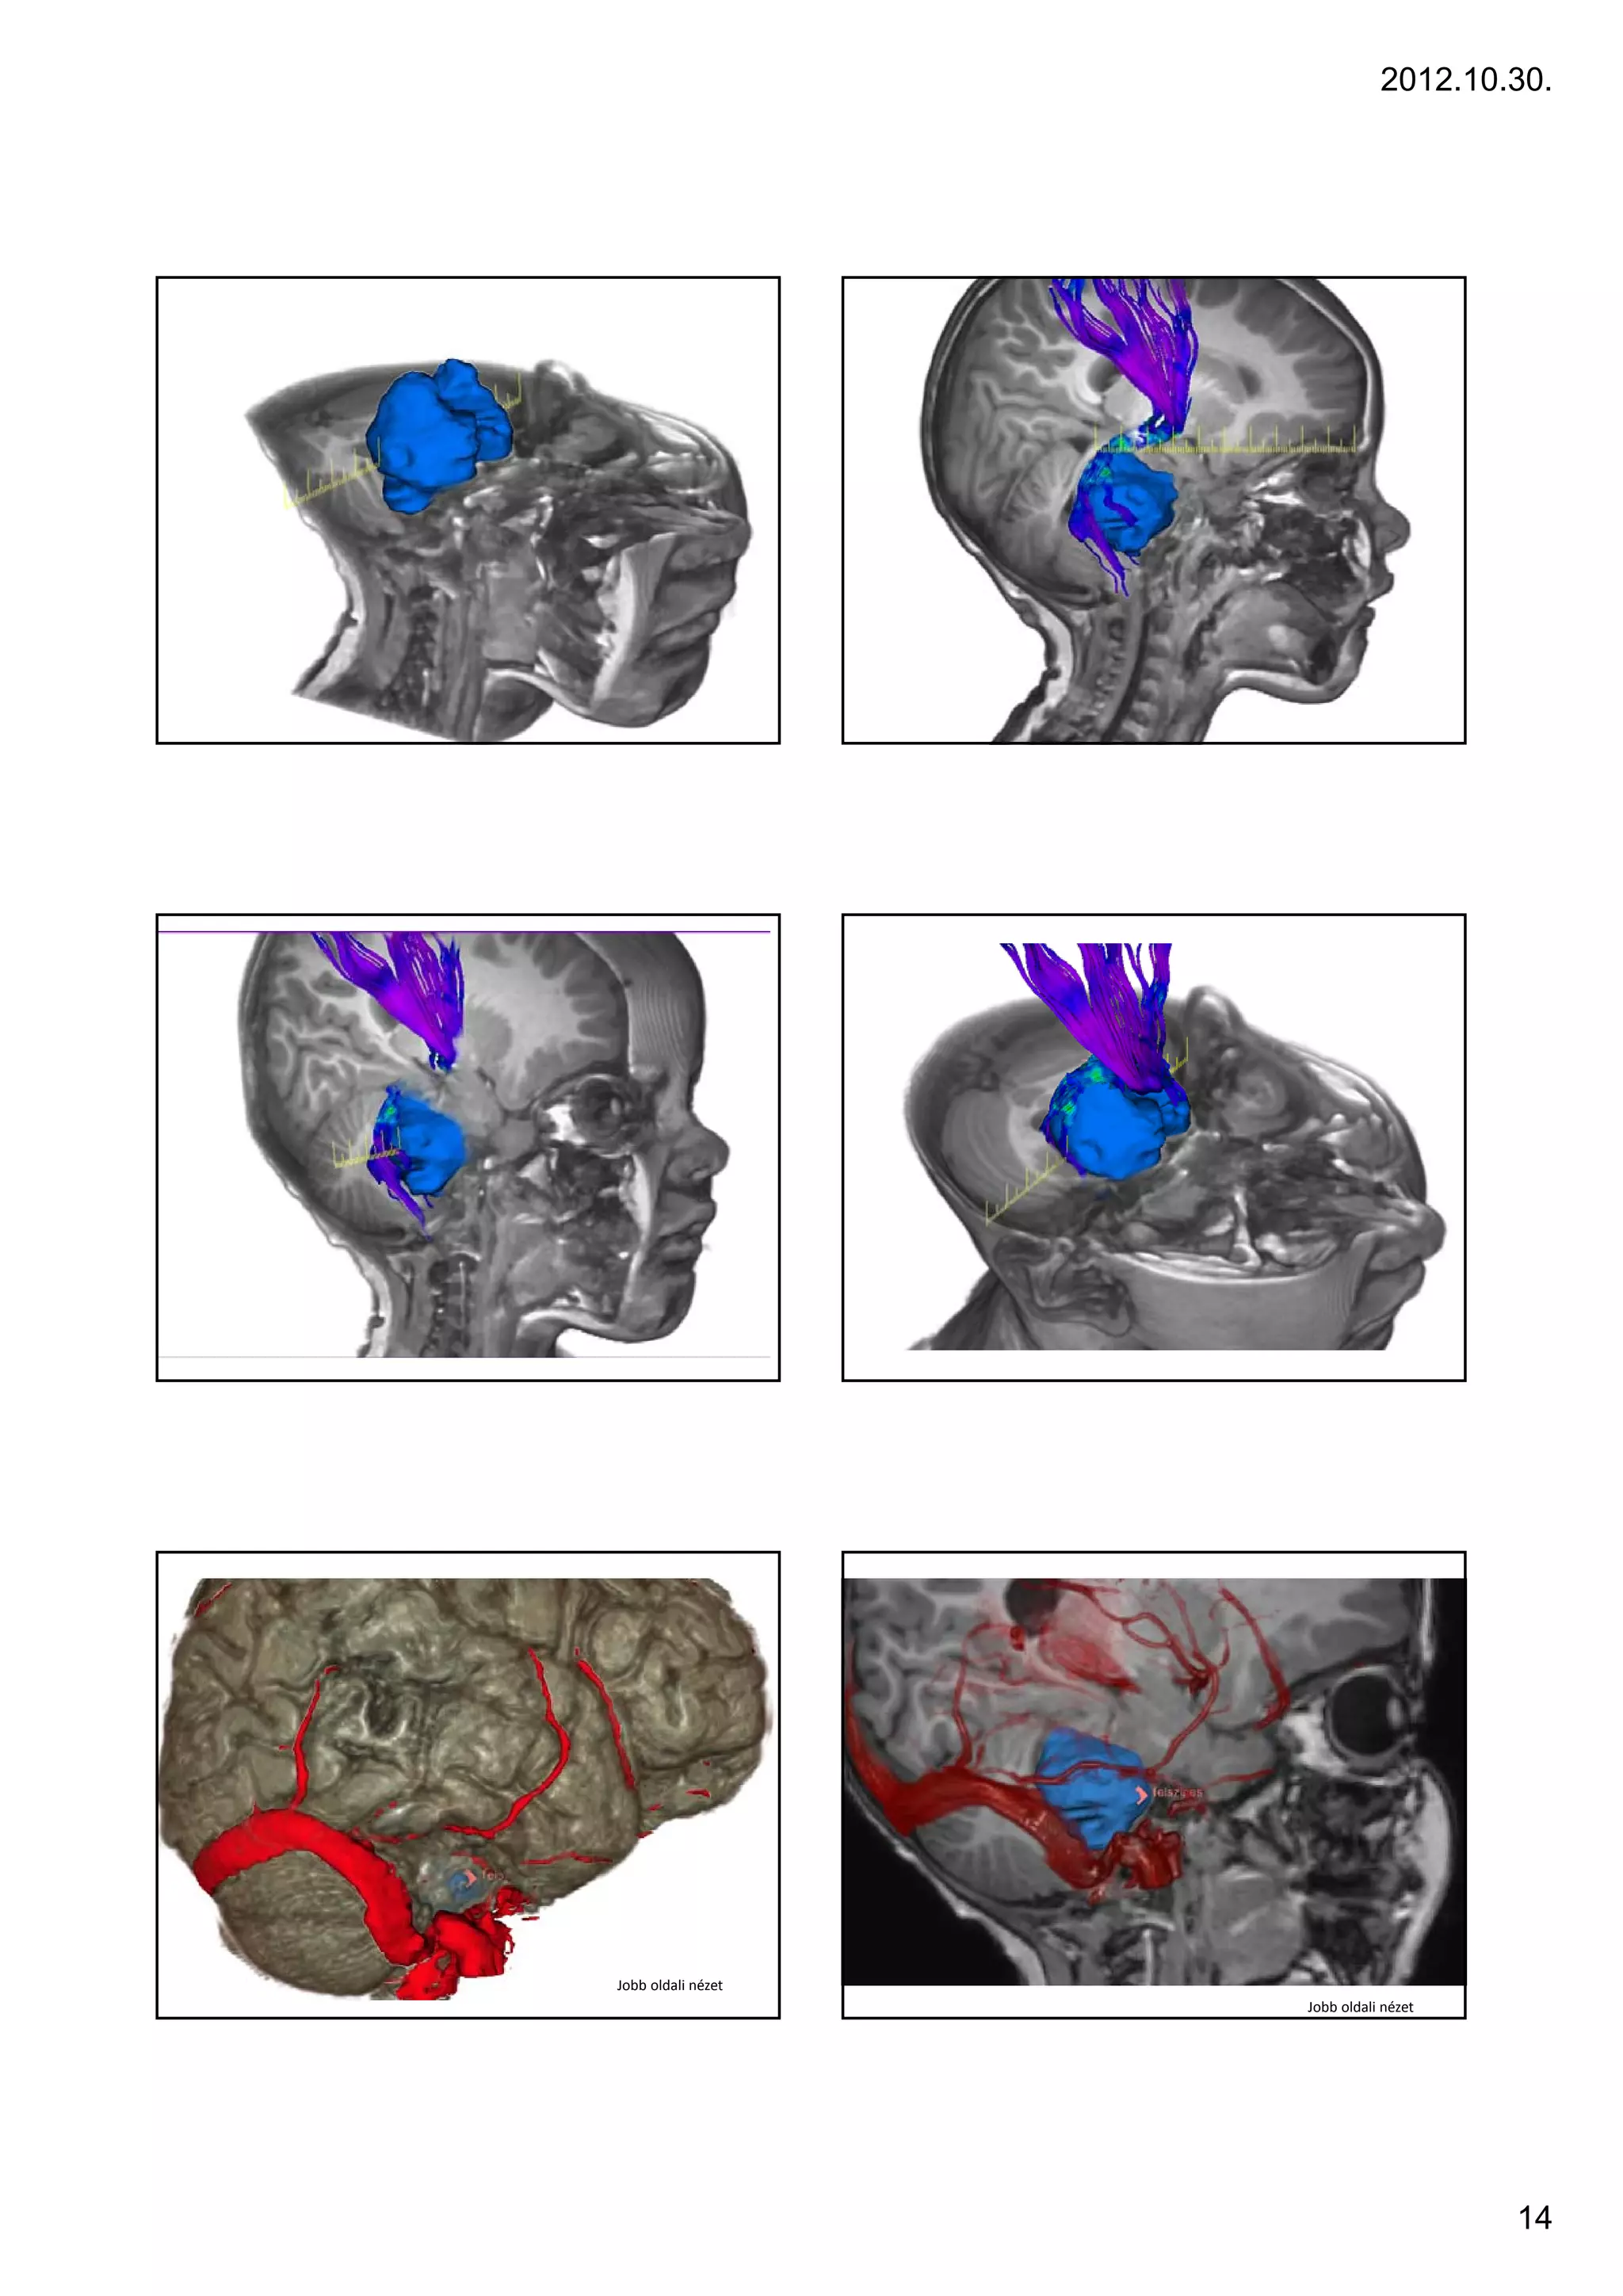

arise from the midbrain or medulla.                                                3 yr, F, ICP signs, cerebellum – tonsillar herniation

2012.10.30.

13

Jobb oldali nézet

14